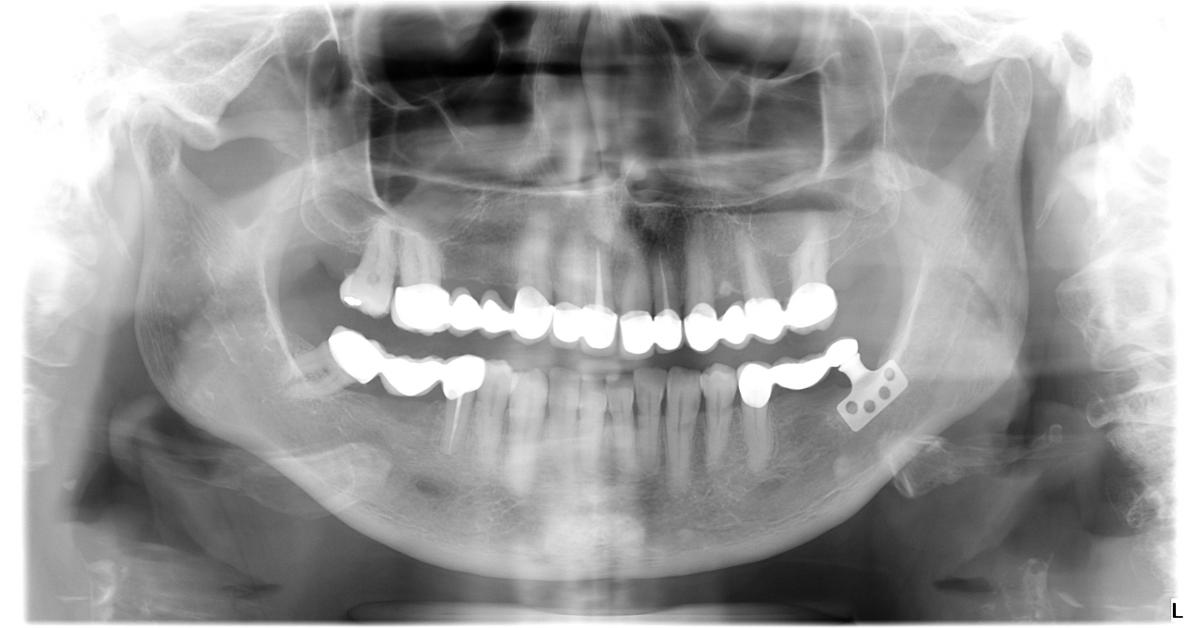

Figure 1 from Primary stability and selftapping blades biomechanical Blade Dental Definition surgical scalpels are fundamental tools in the world of medicine, serving as the primary instruments for incisions during surgical. The face, the lateral surfaces, the cutting edge and the back. Ideal for precise cuts and incisions. hand instruments are single or double ended. from a chronological standpoint, this invention pertains to the innovations in implant dentistry of. Blade Dental Definition.

Figure 1 from Minimally invasive piezosurgery for a safe placement of Blade Dental Definition surgical scalpels are fundamental tools in the world of medicine, serving as the primary instruments for incisions during surgical. from a chronological standpoint, this invention pertains to the innovations in implant dentistry of the 1960s. hand instruments are single or double ended. Favored for gingivectomy and other. Ideal for precise cuts and incisions. The face, the lateral. Blade Dental Definition.

tooth blade implant Google Search Dental implants, Dental, Dentist Blade Dental Definition here's a snapshot of popular blades used in dental surgeries: from a chronological standpoint, this invention pertains to the innovations in implant dentistry of the 1960s. hand instruments are single or double ended. The face, the lateral surfaces, the cutting edge and the back. Favored for gingivectomy and other. Ideal for precise cuts and incisions. the. Blade Dental Definition.